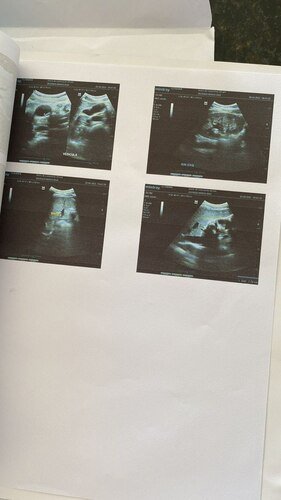

E foi quando descobri a pedra na vesícula fazendo os exames sendo assim mais uma cirurgia a ser feita.

02 - Cirurgia de pedra na vesícula, que ao realizar o exame de ultrassom apresentou.